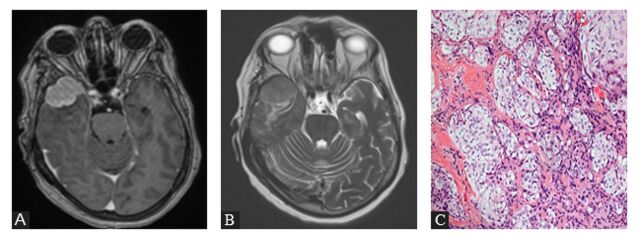

Abstract Image